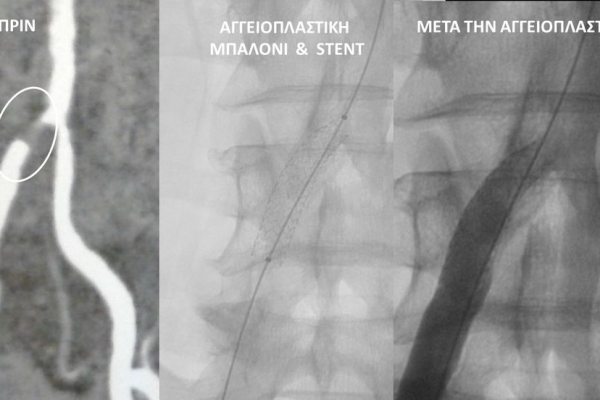

- Η αγγειοπλαστική των αρτηριών είναι μία μη χειρουργική επέμβαση που αποσκοπεί στη διάνοιξη των στενωμένων ή αποφραγμένων αρτηριών. Γίνεται με την ίδια τεχνική όπως και αγγειογραφία. Η αγγειοπλαστική των αρτηριών μπορεί να γίνει είτε με απλή διάνοιξη της αρτηρίας που εμφανίζει στένωση με μπαλόνι ή και να συνοδευθεί από τοποθέτηση ενδαγγειακής πρόθεσης (stent).